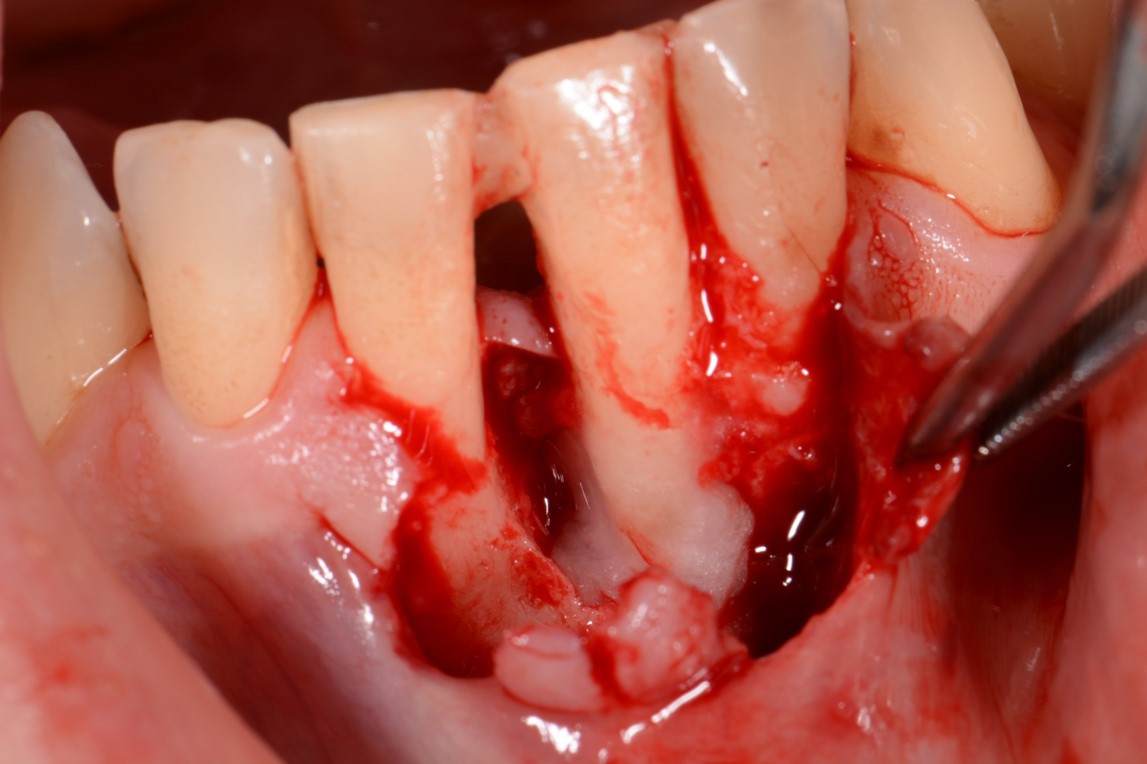

04/12 - Application of Straumann® Emdogain® to the exposed root surface.Two-wall intrabony defect treated using cerabone® and Straumann® Emdogain® - Dr. D. Rakasevic & Prof. Dr. S. Jankovic